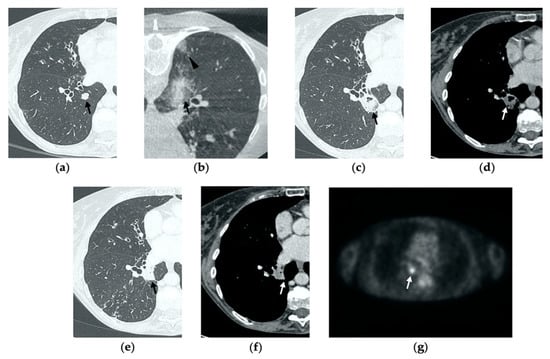

Figure 5. 77-year-old-woman with pulmonary metastasis from CRC in the right lower lobe. (a) Axial CT images prior to treatment (black arrow). (b) Prone cone-beam CT image post-MWA shows GGO of the ablation site (black arrow) and alveolar hemorrhage along the needle tract (arrowhead). (c,d) Axial 1-month follow-up CT shows a subpleural consolidation with well-defined margins, inner hypoattenuating bubbles, a central cavitation (black arrow) and no contrast enhancement (white arrow). (e,f) Axial 6-month follow-up CT images demonstrate resolution of the cavitation, decrease in size of the consolidation (black arrow) and focal uptake of contrast material (white arrow) consistent with a diagnosis of residual disease. (g) The diagnosis is confirmed by PET/CT performed at 7 months (white arrow).

At all stages of follow-up, the appearance of either central or peripheral nodular or irregular enhancement should be considered as residual or recurrent disease (Figure 4f and Figure 5f), since the ablated area undergoes fibrous transformation, and it should not show contrast enhancement, except for the persisting peripheral safe zone [7,15].

The most common complications to consider after lung MWA are pneumothorax (38%), pleural effusion (3–6%) and parenchymal hemorrhage (3–6%), which in most cases present a benign course without any consequences for the patient [7,10,14,21,25]. Since these represent frequent findings in clinical practice in most hospitals, we decided to describe a rare complication (0.5%) that often risks being overlooked: bronchopleural fistula (BPF) [25].

BPF is defined as communication between a bronchus and the pleural space through the ablation zone (Figure 6e,f). The management of this complication is challenging, since treatment may require insertion of a percutaneous drainage or eventually surgery, bronchoscopic or interventional procedures. As a result, BPF represents an extremely rare though potentially severe complication and it should be suspected in cases of delayed or persistent pneumothorax, detected with chest X-ray, respectively, during early and late follow-up CTs (Figure 7) [26].

BPF commonly occurs with hydropneumothorax, and it should not be mistaken with a bronchial fistula, which is a communication between a bronchus and a cavitation in the ablation area and usually resolves uneventfully [26].